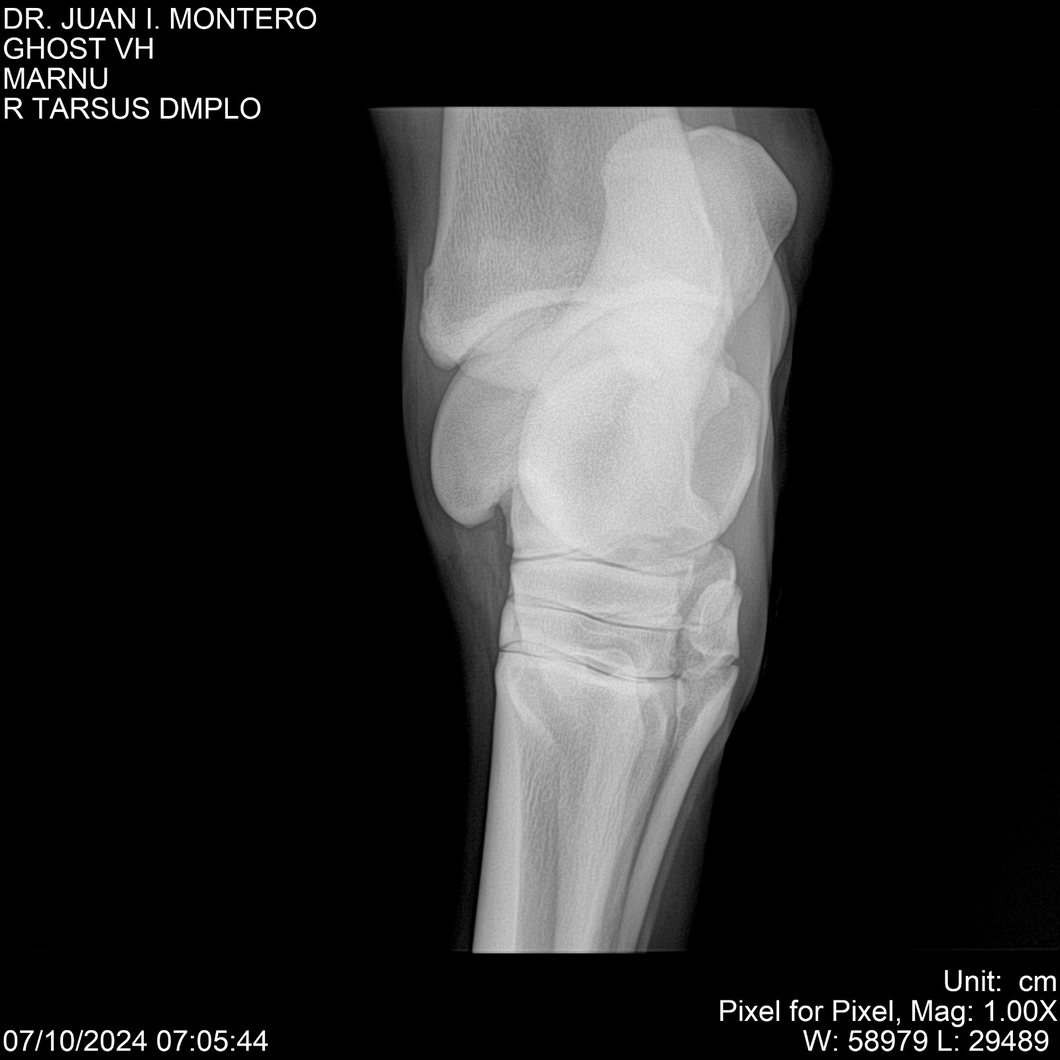

LOTE 15, GHOST VH 🔥 🔥 🔥 Lote Anterior Volver al remate Lote Siguiente Ficha Contacto Montevideo - Ficha del Lote Identificador: #282525 Categoría: Yeguarizos Montevideo - 69 Visualizaciones ClicData Contacto Empresa: Abelenda N. R., Walter Hugo Nombre*: Teléfono* : E-mail* : Mensaje Enviar Registrese gratis Este contenido Exclusivo está disponible sólo para usuarios registrados Ingresar